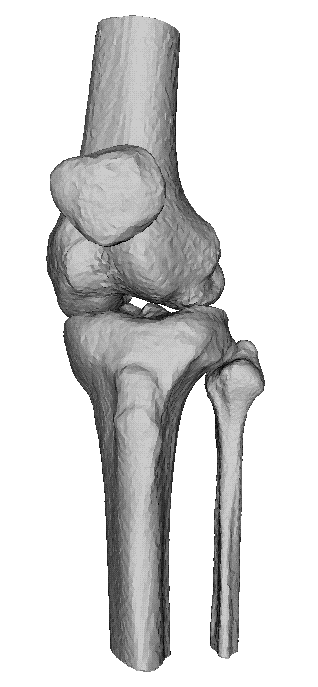

CT van het skelet

Ct knie 3D reconstructieCT Knie

Een Ct-scan van het skelet wordt uitgevoerd wanner er een verdere evaluatie nodigs van een lestel dat gezien is op een klasieke foto. Denk aan fracturen, luxaties e.d., maar ook aan metastasen, arthrose,...Zo kan het bijvoorbeeld zijn dat een letsle niet duidelijk genoeg voorkomt op de foto's endat er dus twijfel bestaat. Maar ook kan het zijn dat een CT-scan noodzaklijk is om een duidelijk beeld te verkrijgen van een uitgebreide fractuur, om verder behandeling te bepalen.

Dankzij de moderne computertechnieken is het niet allen mogelijk om axiale beelden te maken. (lees schijfjes dwars op het lichaam) Maar ook om die beelden te reconstrueren tot een 3D-model. Dit geeft vaak een duidelijk beeld van het bot, en zijn letsel.